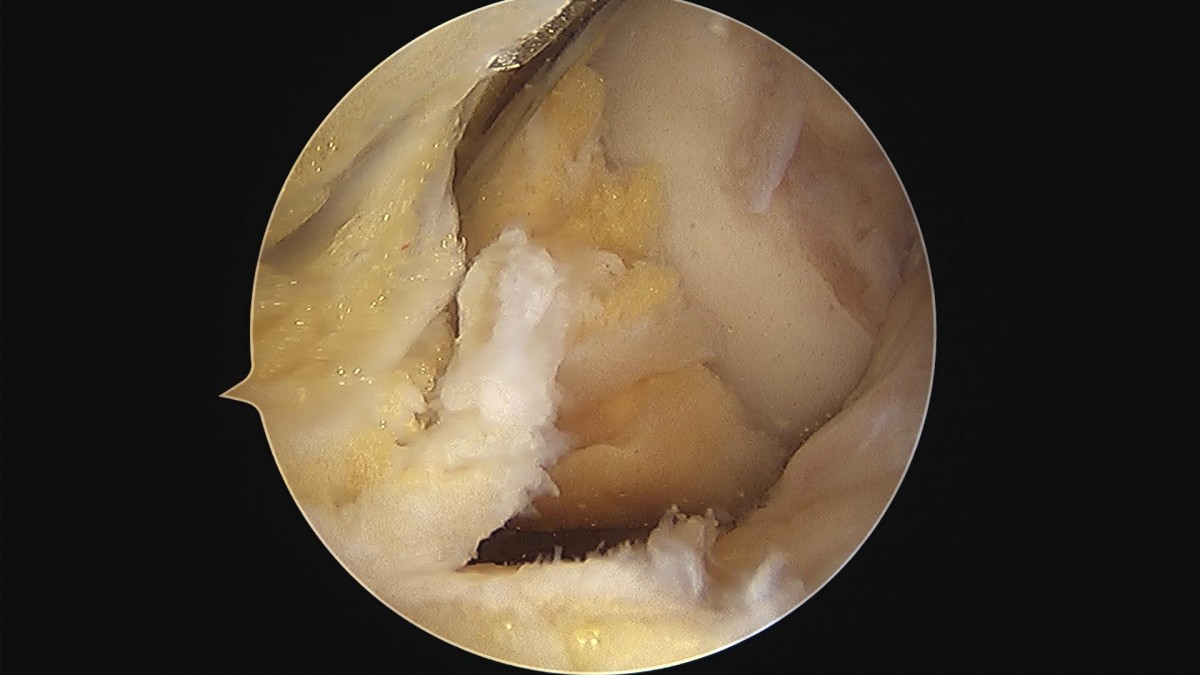

이재상원장님 무릎 내측 반월상 연골판 부분절제술 및 경골 교정술 정순O 환자